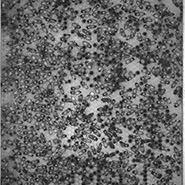

Pathogens are a major factor affecting the evolution of primates. We know very little about how historical pandemics have affected the genomes of different populations. This image results from research that examines how genetic variation and historical exposure to one of the most virulent pathogens known in human history, the plague, has affected immune system evolution and human health.

In the center of this image we see human white blood cells (labeled blue) confronted with bacteria. To protect the body from this invader, the cells capture the bacteria by throwing nets made from their own DNA. The cells are laid over tracks that evoke those seen in bubble chambers, another innovation used by researchers to see into the smallest spaces and understand movement and action on the smallest scales.